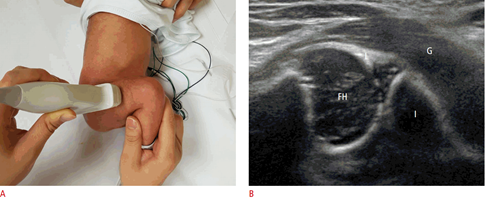

Κλινικοαπεικονιστική εξέταση του νεογνού διευρενώντας οτιδήποτε αποκλίνει της φυσιολογικής ανάπτυξης του ανθρώπινου σκελετού. Κάθε οστό και άρθρωση ελέγχεται επιμελώς και με προσοχή, ώστε να διαπιστωθούν τυχόν ανωμαλίες στην κίνηση ή ακόμα και έλλειψη οστού. Το υπερηχογράφημα χρησιμοποιείται επικουρικά για την διαπίστωση της ομαλής διάπλασης του νεογνικού ισχίου.

Καλύπτεται ένα ευρύ φάσμα παθήσεων με την κλινική εξέταση που οι περισσότερες μπορεί να διαφύγουν της αρχικής εξέτασης μετά την γεννά ή να αναπτυχθούν τις πρώτες εβδομάδες της ζωής (π.χ. περονιαία ημιμέλεια, ραιβοϊπποποδία, ραιβόκρανο, αναπτυξιακή δυσπλασία ισχίου είναι ενδεικτικά κάποιες από αυτές). Η αναπτυξιακή δυσπλασία του ισχίου αποτελεί δε μία σοβαρή πάθηση στον Ελλαδικό χώρο, ιδιαίτερα σε πρωτότοκα θήλεα, πολύδυμες κυήσεις με ολιγοϋδράμνιο και σε νεογνά που γεννήθηκαν με ισχιακή προβολή. Η αναπτυξιακή δυσπλασία διαπιστώνεται με κλινικό έλεγχο και επιβεβαιώνεται ή αποκλείεται με υπερηχογράφημα, που πραγματοποιείται στις 4 έως 6 εβδομάδες μετά την γέννηση είτε με ακτινογραφικό έλεγχο μετά τον 3ο μήνα του νεογνού.

Η ορθοπαιδική εξέταση που συμπληρώνεται με το υπερηχογράφημα ισχίων είναι απολύτως ασφαλής και εντελώς ακίνδυνη, καθώς δεν επιβαρύνει με ακτινοβολία τον οργανισμό του νεογνού, ούτε χρειάζεται αναλγησία ή κάποια άλλη ιατρική παρέμβαση.